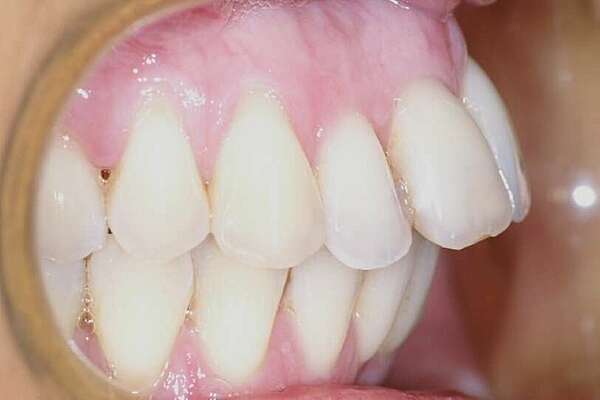

Reprise de récidive par gouttières

Reprise de traitement d'un patient ayant eu un traitement dans l'enfance